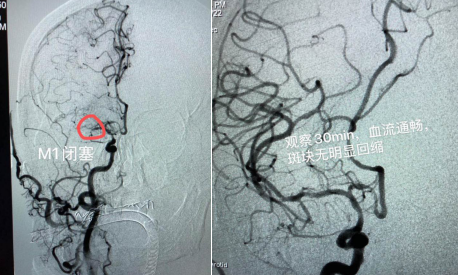

該患者男性,69歲,既往有高血壓、糖尿病、腦梗死等病史;主因“突發(fā)左側(cè)肢體活動(dòng)障礙5小時(shí)”入院;患者入院時(shí)神志嗜睡,煩躁不安,言語(yǔ)含糊,雙側(cè)眼球向右側(cè)凝視,雙側(cè)瞳孔等大、等圓,對(duì)光反射( + );左側(cè)中樞性面舌癱;左側(cè)肢體肌力0級(jí),右側(cè)肢體肌力5級(jí), NIHSS評(píng)分15分。入院后,立即啟動(dòng)卒中綠色通道,在頭顱CT排除腦出血后,進(jìn)行急診頭顱MRI+MRA檢查:右側(cè)顳葉梗死,右側(cè)大腦中動(dòng)脈閉塞。為進(jìn)一步明確病因,決定對(duì)患者實(shí)施腦血管造影+備支架機(jī)械取栓術(shù),盡最大努力挽救患者生命。時(shí)間就是生命!腦病科丁煜主任緊急與患者家屬溝通病情,取得了家屬的同意。在急診科、放射科、麻醉科、重癥監(jiān)護(hù)室、檢驗(yàn)科等多學(xué)科協(xié)作下,以腦病科邢錫熙主治醫(yī)師為首的神經(jīng)介入治療組迅速完成術(shù)前準(zhǔn)備,于入院內(nèi)1小時(shí)進(jìn)入導(dǎo)管室穿刺造影,發(fā)現(xiàn)患者右側(cè)大腦中動(dòng)脈M1遠(yuǎn)端閉塞,遂行支架機(jī)械取栓術(shù),一次性開(kāi)通血管;發(fā)現(xiàn)大腦中動(dòng)脈重度狹窄,在藥物維持血流無(wú)效的情況下,當(dāng)機(jī)立斷行球囊擴(kuò)張,血管順利3級(jí)開(kāi)通,觀察半小時(shí)血流通暢。

術(shù)前血管閉塞 術(shù)后血管3級(jí)開(kāi)通

術(shù)后患者轉(zhuǎn)入重癥監(jiān)護(hù)室,術(shù)后6小時(shí)患者意識(shí)完全清醒,術(shù)后3天右側(cè)肢體肌力恢復(fù)至3級(jí),轉(zhuǎn)入普通病房,經(jīng)過(guò)半個(gè)月的精心治療,患者右側(cè)肢體肌力基本恢復(fù)正常,康復(fù)出院。